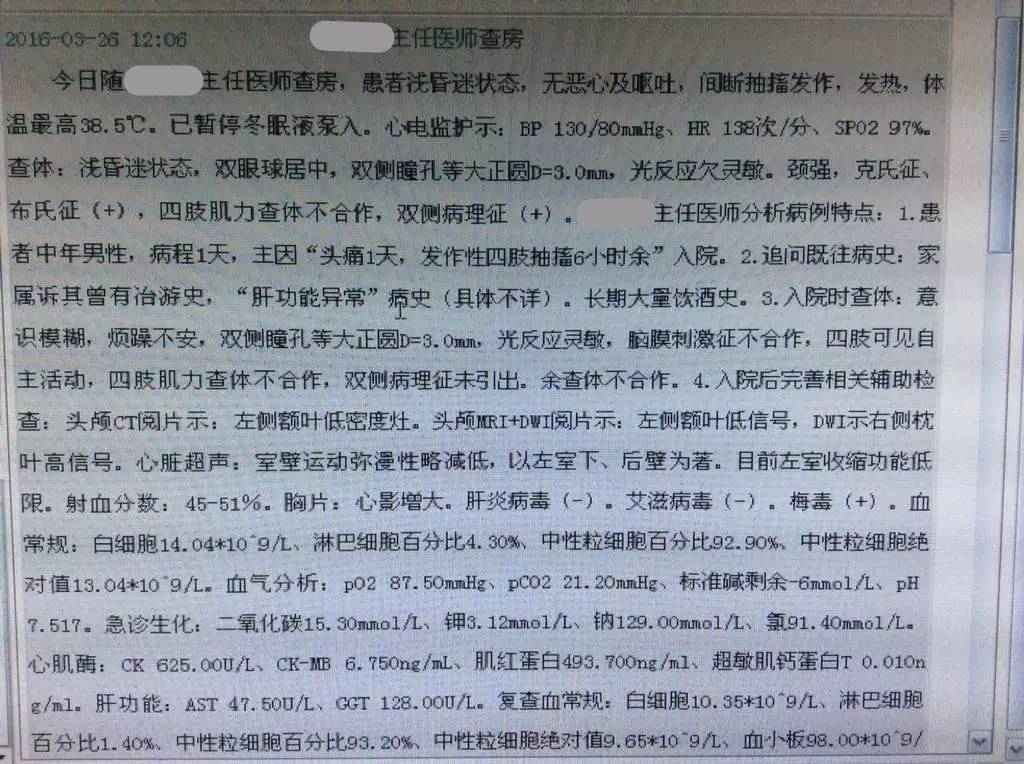

患者:男性,36岁,主因“头痛1天,发作性四肢抽搐6小时余”于2016年3月24号入院。

现病史:患者于入院1天前无明显诱因由家属发现头痛,头痛性质及部位不能提供,家属诉其头痛难以耐受,伴恶心、未呕吐,随后逐渐出现烦躁不安、胡言乱语等情况,不能听懂及理解他人谈话内容,无肢体活动不灵,无意识丧失及二便失禁,未予以重视,患者上述症状持续无缓解。入院6小时前患者无明显诱因出现发作性肢体抽搐,家属诉当时患者意识不清,双上肢屈曲、双下肢伸直,头向左侧偏斜,双眼上视、牙关紧闭、口吐白沫、小便失禁,患者肢体抽搐持续约10分钟自行停止,抽搐发作后仍烦躁不安、胡言乱语,再发后未予以任何处置,急来我院,行头颅CT示左额叶低密度影,急诊以“头痛、精神行为异常原因待查”收入我科。患者自发病以来,精神行为异常,饮食睡眠差,大小便正常。

既往:13年前头颅外伤史。

查体:生命体征平稳,意识模糊,双瞳孔正大等圆,光反射灵敏,余脑神经查体欠合作。四肢肌力、肌张力检查欠合作,双侧腱反射存在对称,感觉运动查体欠合作,双侧病理征(+)。颈抵抗。

辅助检查:

2016-3-24血常规示,白细胞计数10.35×109/L,淋巴细胞百分比1.4%,中性粒细胞百分比93.2%,中性粒细胞绝对值9.65×109/L。

2016-3-25生化全项示,AST47.5U/L,GGT128U/L。血沉80mm/h,CRP453mg/L。

2016-3-26甲功三项(-),术前四项(-),梅毒螺旋体抗体(+)。

2016-3-25腰穿压力>300mmH2O,细胞计数80×106/L,脑脊液蛋白5.432g/L,葡萄糖0.03mmol/L,氯化物112.3mmol/L,脑脊液IgG601mg/L。脑脊液墨汁染色(-),抗酸染色(-),间皮细胞30%,单核细胞30%,多核细胞40%。

1.青壮年,急性起病,以头痛、癫痫、脑膜炎体征为主,同意中枢神经系统感染的诊断。

2.脑脊液改变不除外结核感染,但头MRI改变非典型结核影像。左额叶病灶似以脑外为主,波及对侧及额窦,不排除慢性感染病灶急性破入蛛网膜下腔。左额叶病灶与脑脊液信号等信号,DWI也为低信号,说明非急性病变。